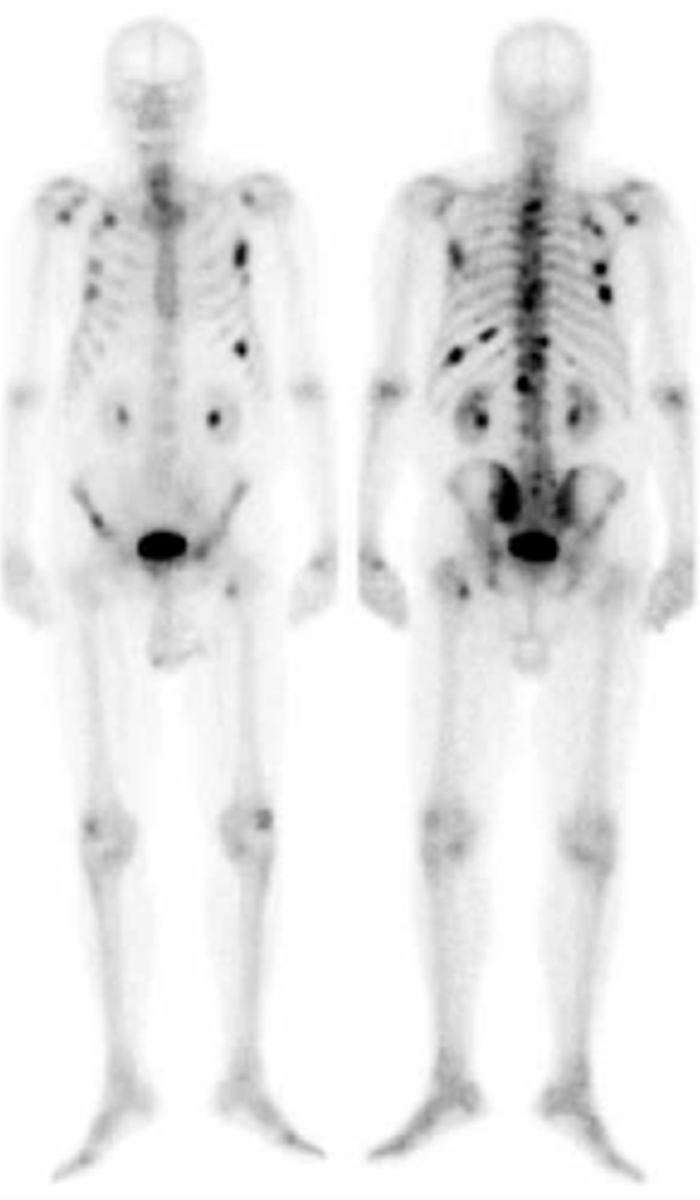

The most likely cause of this abnormal bone scan would be

the patient has widespread metastatic disease

Typically, skeletal metastatic disease has multiple focal lesions throughout the skeletal, with greatest involvement generally in the axial skeleton (true/false)

True